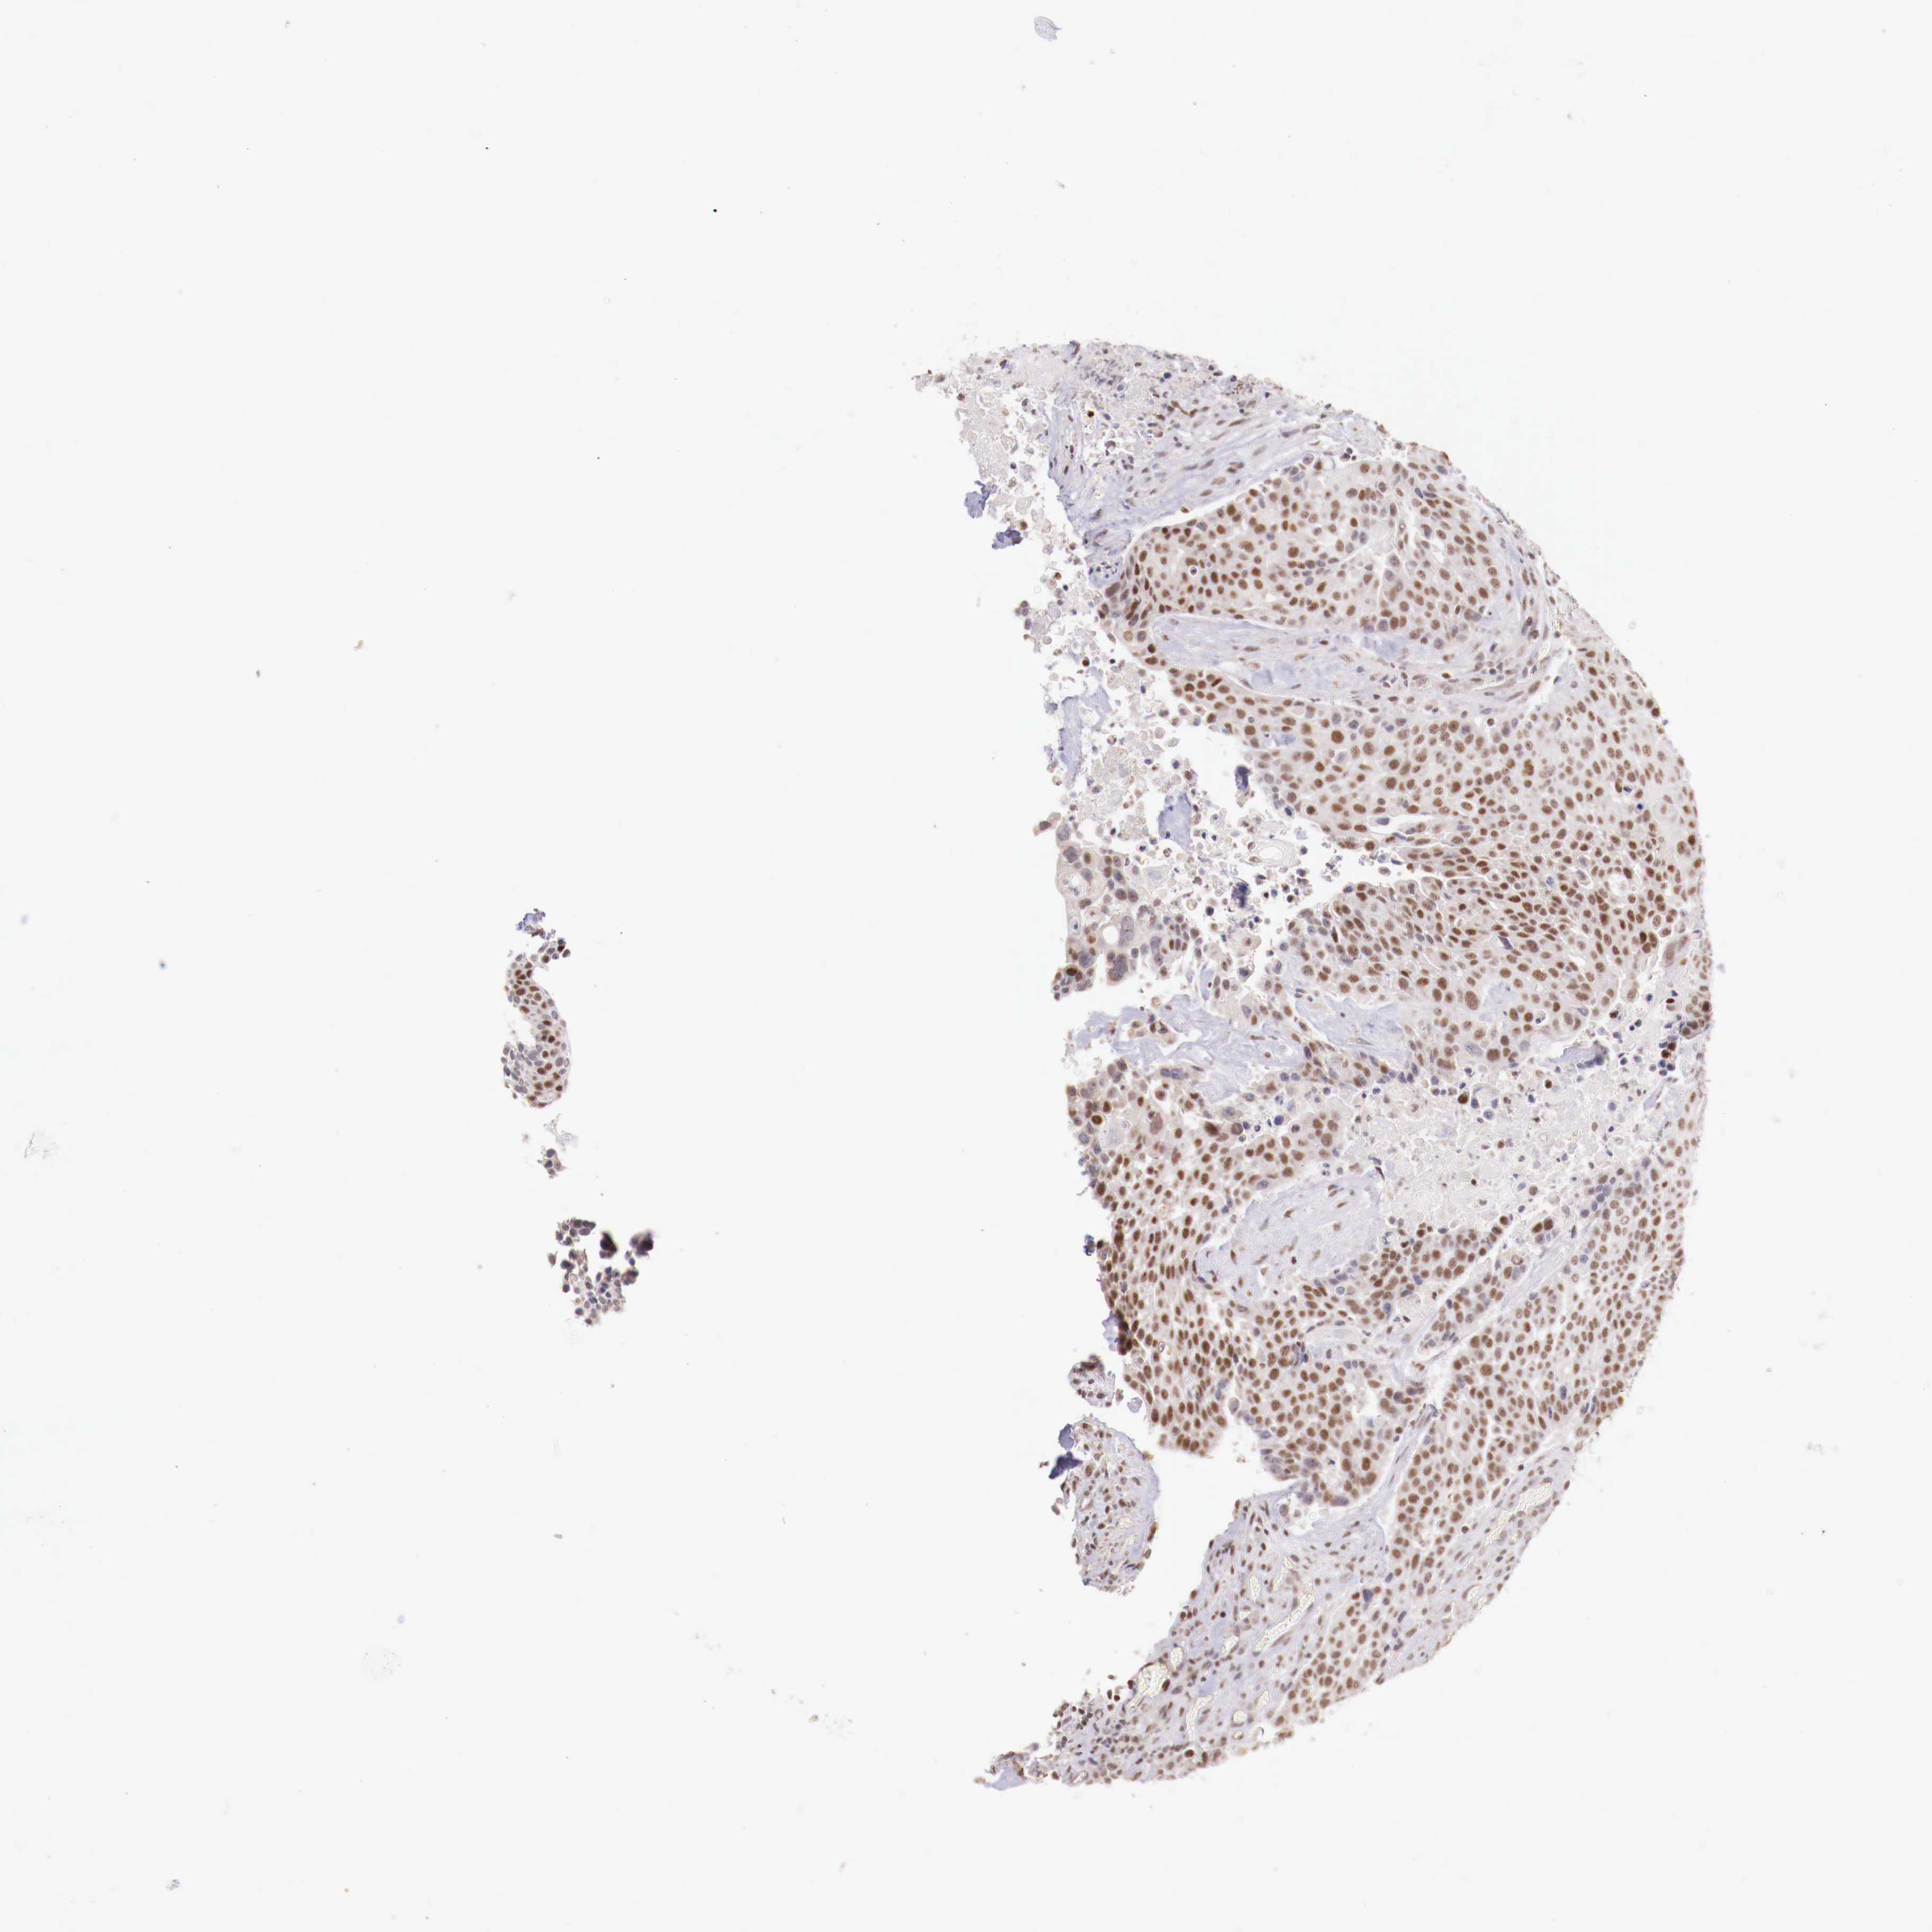

UROTHELIAL CANCER - Protein expressioni

A mouse-over function shows sample information and annotation data. Click on an image to view it in a full screen mode. Samples can be filtered based on level of antibody staining by selecting one or several of the following categories: high, medium, low and not detected. The assay and annotation is described here.

Note that samples used for immunohistochemistry by the Human Protein Atlas do not correspond to samples in the TCGA dataset.

Antibody stainingi

Antibody staining in the annotated cell types in the current human tissue is reported as not detected, low, medium, or high, based on conventional immunohistochemistry profiling in selected tissues. This score is based on the combination of the staining intensity and fraction of stained cells.

Each image is clickable and will lead to virtual microscopy that enables deeper exploration of all samples and also displays staining intensity scores, fraction scores and subcellular localization as well as patient and tissue information for each sample.

Antibody HPA001853

Antibody HPA012292

Antibody CAB000330

Staining

High

Medium

Low

Not detected

Intensity

Strong

Moderate

Weak

Negative

Quantity

>75%

75%-25%

<25%

None

Location

Nuclear

Cytoplasmic/membranous

Cytoplasmic/membranous,nuclear

Urothelial carcinoma, High grade

Urothelial carcinoma, Low grade